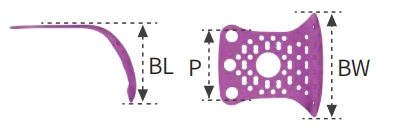

T1 Type

-

Proximal Width: 7 mm

-

Buccal Width (BW): 12 mm

-

Buccal Length: 9 mm

-

Lingual Height: —

-

Thickness: 0.2 mm